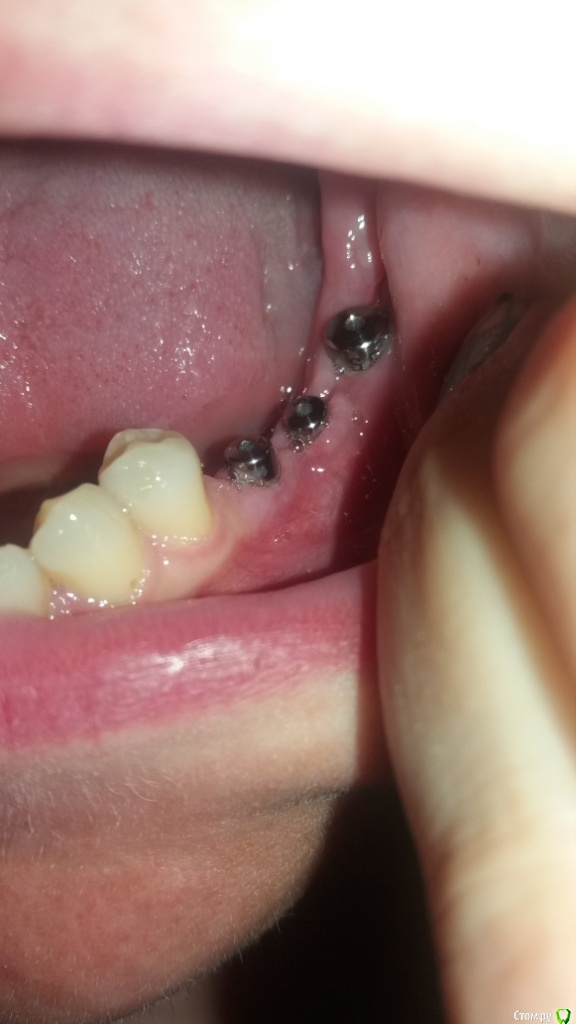

Oksana-p Опубликовано 15 июня, 2016 Автор Поделиться Опубликовано 15 июня, 2016 Вот такая ситуация сейчас..... Ссылка на комментарий

Oksana-p Опубликовано 25 июля, 2016 Автор Поделиться Опубликовано 25 июля, 2016 ДД. Коронки с розовой десной опять не понравились ортопеду. Очень уж длинные коронки получаются. Не знает, что со мной делать... Пытается как-то выкрутиться. Да за эти 2,5 месяца после пересадки десны похоже ничего от нее не осталось. Скоро опять будет виден верх импланта. А такой кусок вырезали... Вот фото сейчас во рту. Другой ортопед предложил два варианта - сделать опять пластику десны (хотя там мало что осталось) или удалить эти импланты, сделать костную пластику и т.д. Но в Минске не знаю куда обращаться. В клинике, где мне ставили, тот хирург уже уволился. Да они и не хотят ничего переделывать, т.к. считают что у меня все отлично. Ув. форумчане, посоветуйте что лучше сделать. Ссылка на комментарий